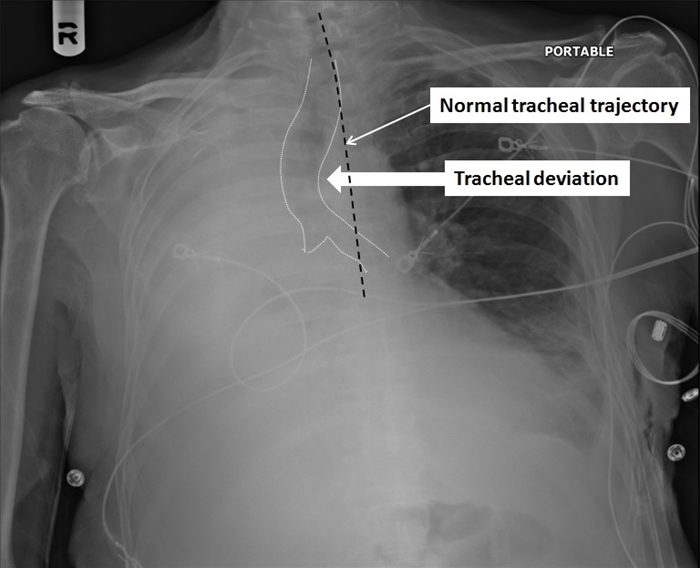

Tracheal Deviation

This patient's decreased breath sounds, hemithorax opacification on the right, and deviation of the trachea toward the opacified side are suggestive of a collapsed lung due to bronchial obstruction. Complete collapse of a lung usually occurs following obstruction of a mainstem bronchus (eg, central lung tumors in chronic smokers). As the air trapped in the lung gradually gets absorbed into the blood, there is loss of lung volume due to alveolar collapse (ie, atelectasis), which causes the trachea to deviate toward the affected side. Other mediastinal structures (eg, heart, esophagus, great vessels) may also shift in the same direction. The loss of radiolucent air, combined with shifting of organs into the hemithorax, appears as a completely opacified hemithorax on chest x-ray.